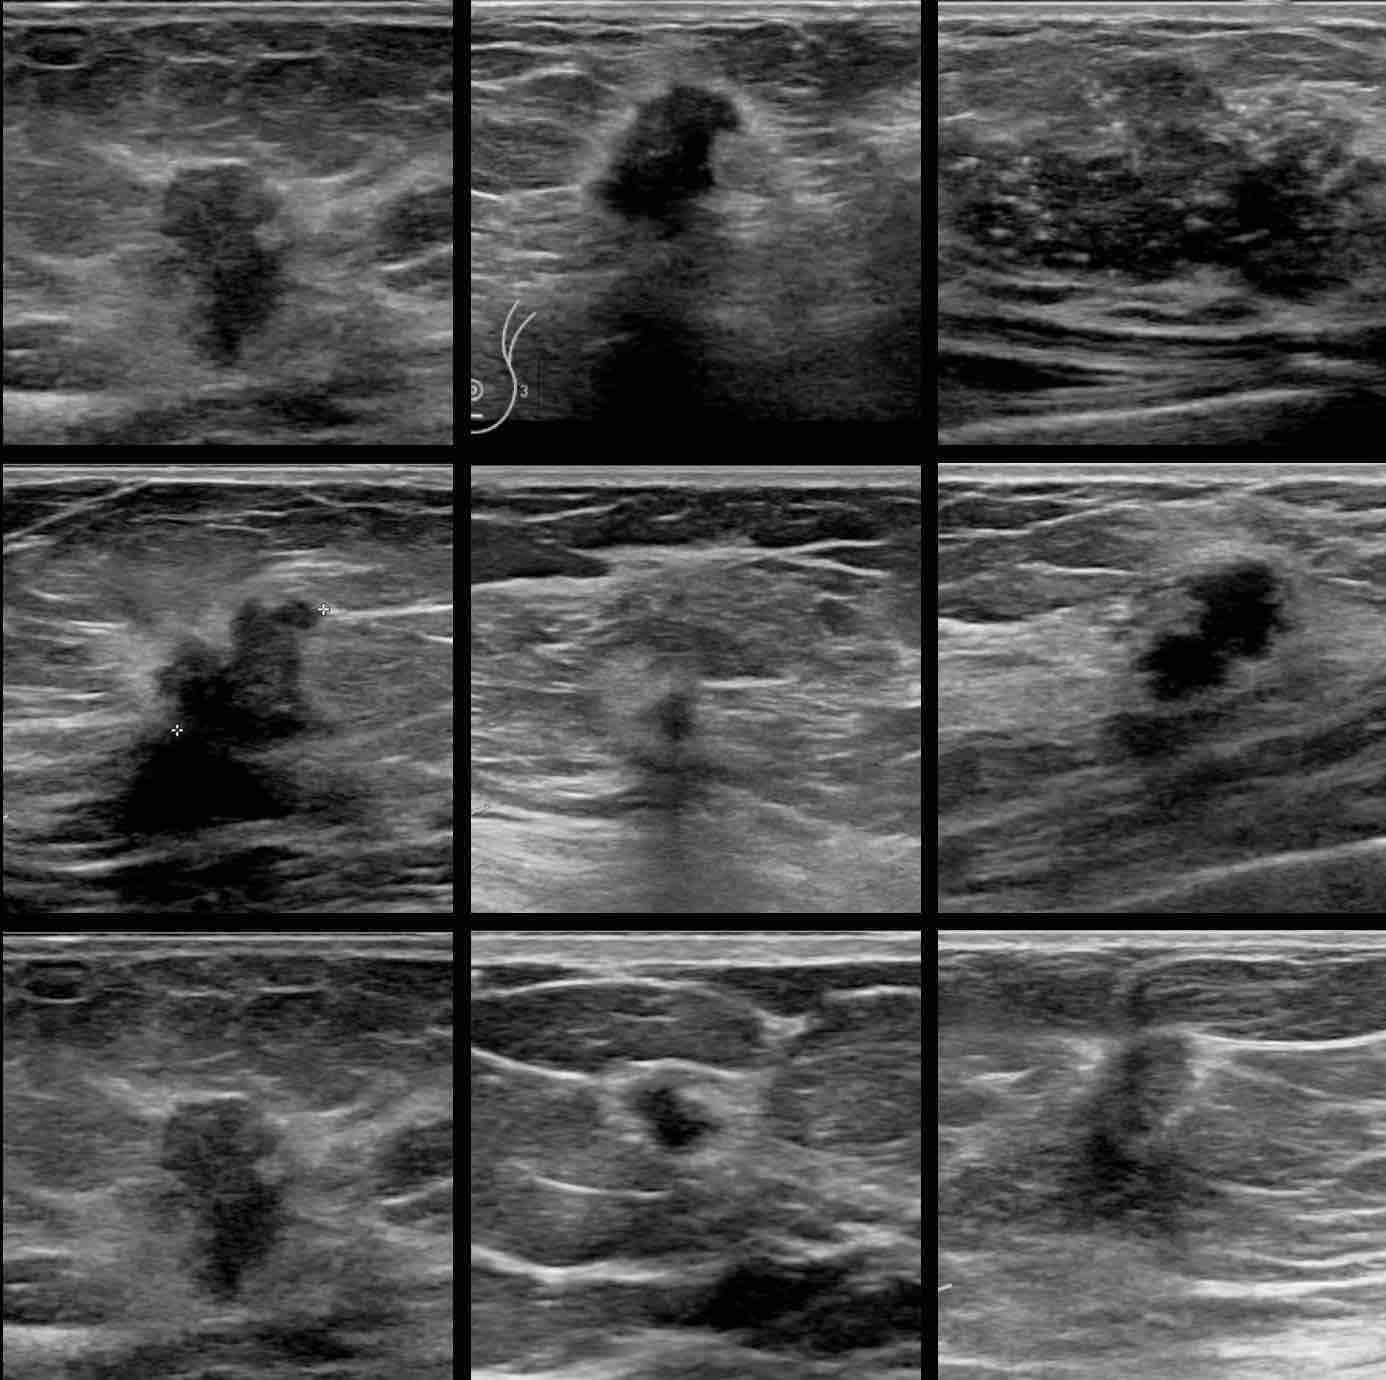

From www.researchgate.net

Description of the sonographic appearance exhibited by different breast Painful Breast Lump Ultrasound While cysts are typically not cancerous, a solid lump may. If the lumpiness can be felt throughout the breast and feels like your other breast, then it’s likely normal breast tissue. I learned i have dense breast tissue, which means i may need. To diagnose a breast cyst, your women’s health provider will discuss your symptoms and health history and. Painful Breast Lump Ultrasound.